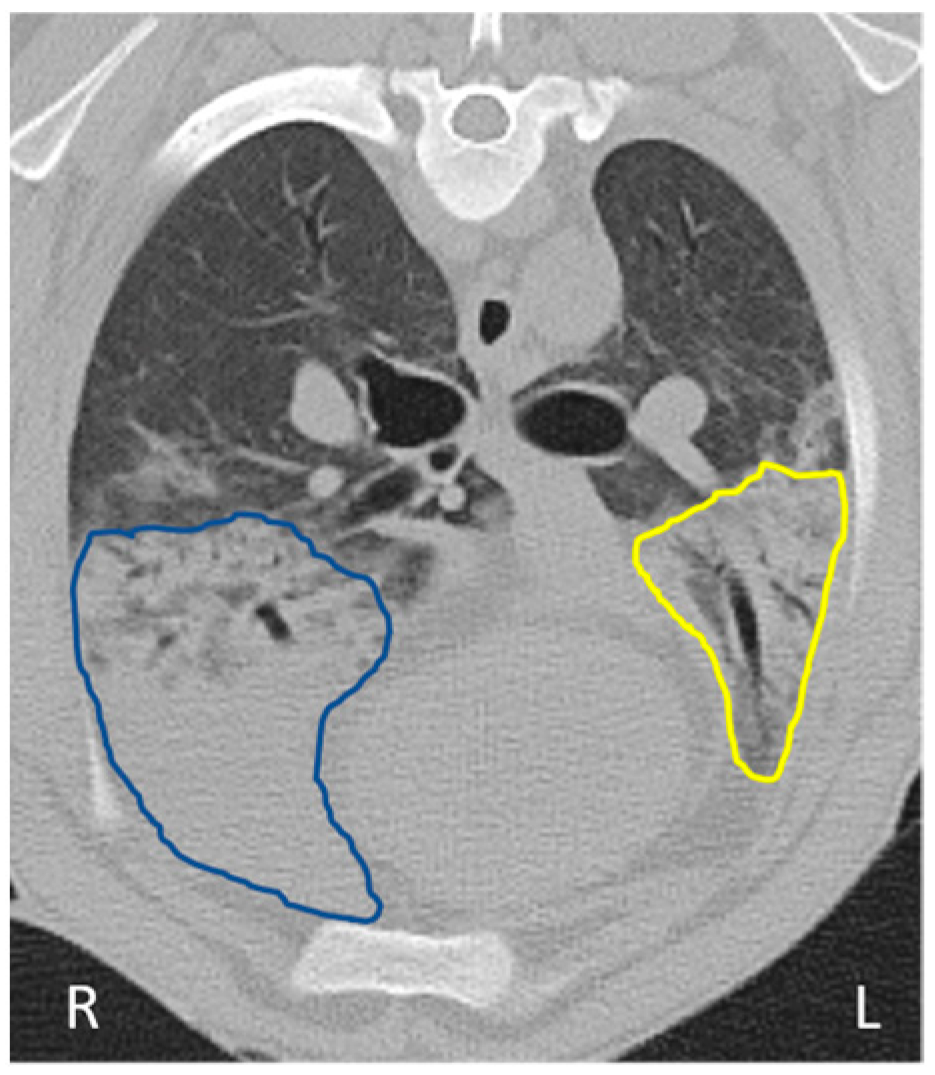

2.4. Trans-Thoracic Ultrasound Scanning

3.3. Ultrasound and CT Are Able to Identify Changes Consistent with OPA Diagnosis

3.5. Ultrasound and CT Are Highly Correlated in Their Ability to Track Tumour Development over Time